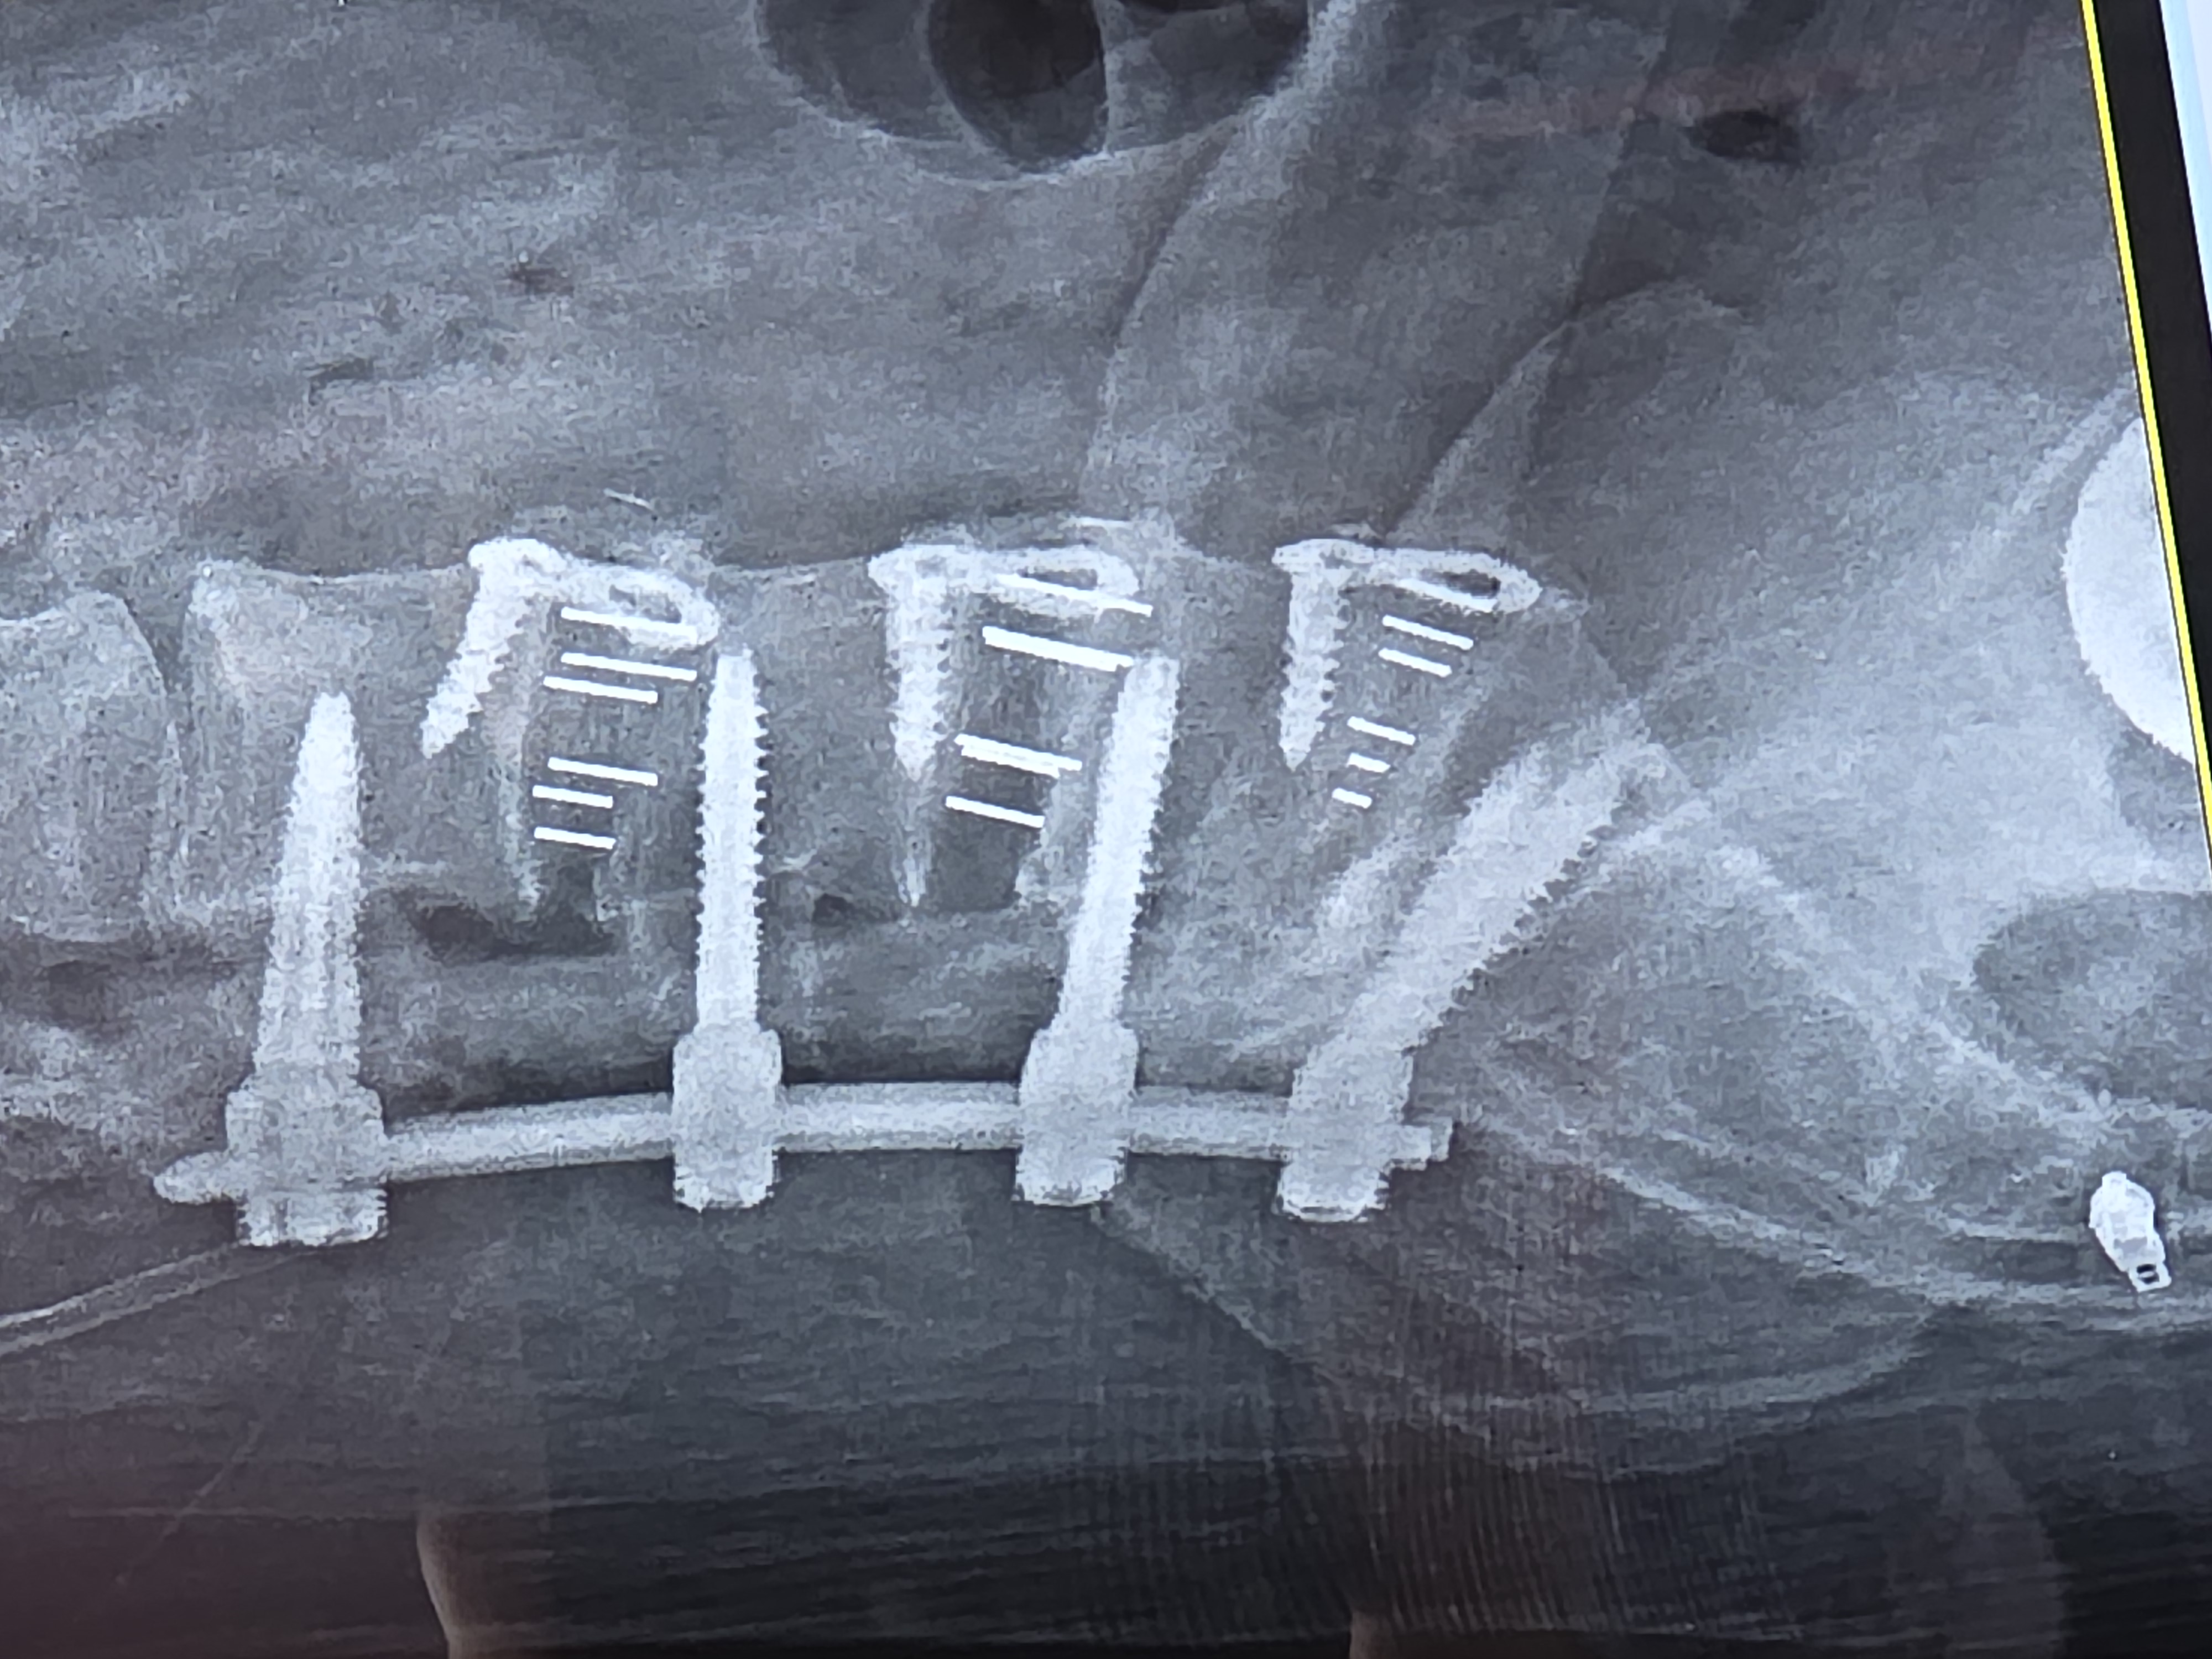

I can probably say more than others and as you read you'll see why.. Met Dr. Courtney in 2021 for bad lumbar accident. First, every time you go, you carry your folder and they give you a gold star...great way to ensure you pay attention. Normally everyone ends with 7, but the record was 17 because it was detailed. I'm over 50 stars. What does that say? Hes bad? No! Says they are very loyal to us. He perforned 360. Lumbar fusion to L3-S1 and he did it but I never got relief. Worsurgeon. wanted another doctorc and delayed and... read more